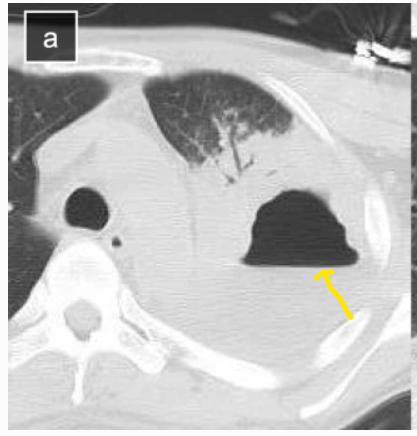

42岁男性,发热,肺脓肿。

美罗培南和万古霉素进行抗生素治疗。持续5天的抗生素治疗,没有显示出令人满意的临床结果。

图10

在CT引导下,在肺脓肿里面放入10Fr猪尾导管,然后引流肺脓肿。然而,只排出42毫升脓液。患者仍然发热,肺部的病灶还增多了。

图11

后来引流管就再也没有脓液出来,患者病情加重,呼吸衰竭,气管插管,上呼吸机!

换大号引流管,直接上28Fr猪尾导管,是以前的大约3倍。

患者上着呼吸机,搞个全麻,双腔管单肺通气,隔离左肺(防止脓液进入),在X线引导下放入大号引流管。

图12

负10cmH2O的压力吸引,8天引流出650毫升脓液,脓液检测到口腔普氏杆菌、血管链球菌和坏死梭杆菌,抗生素治疗降级为舒巴坦钠/氨苄西林钠,5天后脱离呼吸机,第18天取出导管,40天后出院。

7个月后,他的胸部CT证实肺脓肿完全治愈,但遗留了一个薄壁空洞。